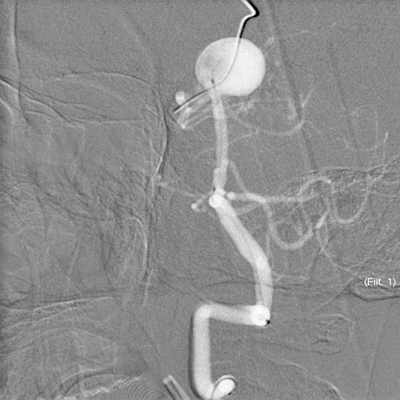

支架导管到位后,释放支架的过程中我们可以看到,具有推送杆无头设计的支架,对于这一类型的动脉瘤治疗非常具有优势。

4枚标记点准确定位,顺利释放支架,经由支架依次填入17枚弹簧圈。术后即刻弹簧圈栓塞满意,支架贴壁性良好。

术后即刻造影我们可以看到,动脉瘤不显影,载瘤动脉通畅。

5天后复查全脑血管造影显示,瘤体栓塞满意,载瘤动脉通畅。